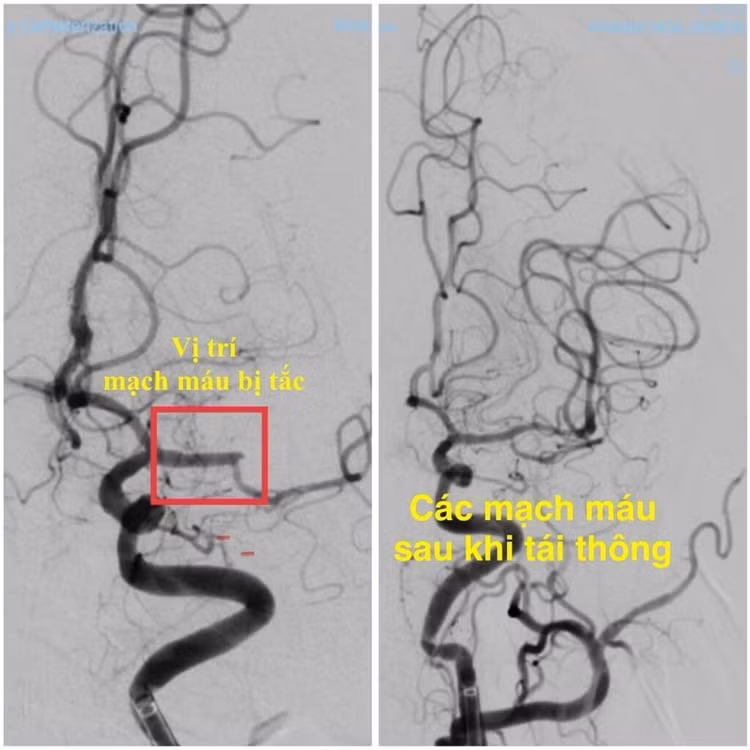

Ngay trong đêm, ê-kíp can thiệp mạch não Khoa Đột quỵ đã nhanh chóng tiến hành can thiệp lấy huyết khối và tái thông hoàn toàn động mạch não giữa trái bằng hệ thống máy DSA. Thủ thuật được thực hiện khẩn trương, chính xác, đảm bảo an toàn cho người bệnh.

Cấp cứu đột quỵ lấy huyết khối cơ học thời gian vàng đột quỵ can thiệp mạch não Bệnh viện Đa khoa Khánh Hòa nhồi máu não cấp - Ảnh BVCC

Hình ảnh mạch máu não trước và sau can thiệp - Ảnh BVCC